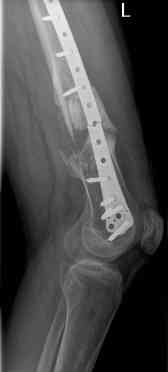

16 yr old boy, high energy motorcycle trauma trauma in July 2005 with:

- hip dislocation + acetabular fracture L

- distal femoral fracture L

- tibial shaft fracture L

- metatarsal fractures L

Nov 06

july 05: LISS femur, LCP plate tibia, double recon. plate post. acetabulum

oct 05: cancellous bone graft femur

aug 06: blade plate + bone graft

nov 06: revision blade plate

feb 07: retrograde nail + bone graft + BMP

may 07: dynamisation nail

sept 07: locking screw removal (max. dynamisation reached)

nov 07: persistant non-union distal femur; other fractures healed uneventfully.